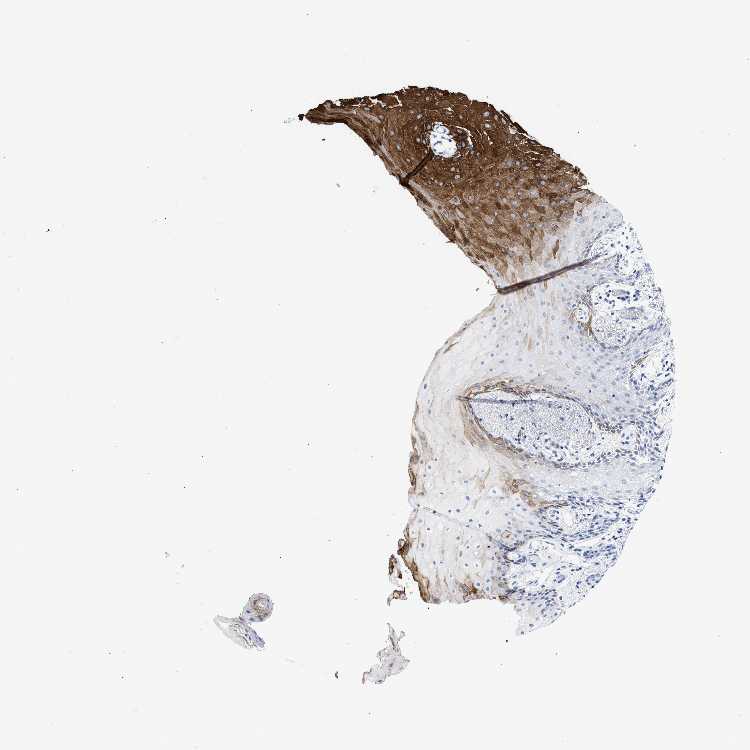

TISSUE PRIMARY DATA ORAL MUCOSA Show tissue menu

ORAL MUCOSA - Antibody stainingi

Antibody staining in the annotated cell types in the current human tissue is reported as not detected, low, medium, or high, based on conventional immunohistochemistry profiling in selected tissues. This score is based on the combination of the staining intensity and fraction of stained cells.

Each image is clickable and will lead to virtual microscopy that enables deeper exploration of all samples and also displays staining intensity scores, fraction scores and subcellular localization as well as patient and tissue information for each sample.

Antibody HPA018221

Squamous epithelial cells Medium